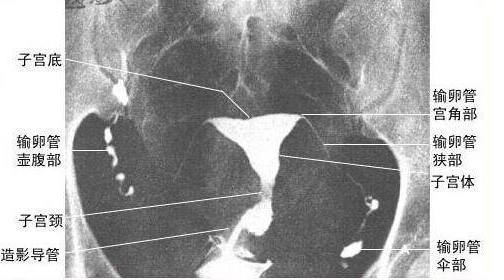

输卵管位于子宫的两侧,为一对细长而弯曲的肌性管道,为卵子与精子结合场所及运送受精卵的通道,内侧与子宫角相连通,开口于子宫腔,称为输卵管子宫口,外端游离呈伞状,开口于腹膜腔,称为输卵管腹腔口,全长8~14cm。输卵管游离的伞部呈漏斗状,漏斗周缘有许多指状突起称输卵管伞,有[拾卵]作用。